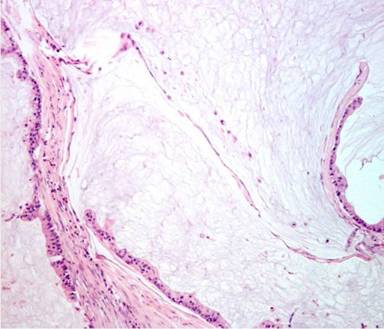

The pathological examination of the specimen demonstrated a colloid carcinoma of the pancreas, 15 cm in diameter, locally invading the posterior gastric wall and the transverse colon. Retroperitoneal resection margins were free of invasion. The microscopic examination found pools of mucin with rows of epithelial mucinous cells showing nuclear atypia, and occasionally adopting a glandular pattern (Figure 2). Associated IPMN with high grade dysplasia (‘in situ’ carcinoma) invading the entire Wirsung duct was also observed. There was no metastatic invasion in any of the lymph nodes retrieved. After evaluation by the multidisciplinary team, no adjuvant chemotherapy was indicated.

Figure 2. Microscopic histopathological examination of the surgical specimen showed the characteristic pools of mucin with rows of epithelial mucinous cells showing nuclear atypia, and occasionally adopting a glandular pattern (H&E; original magnification x10). |